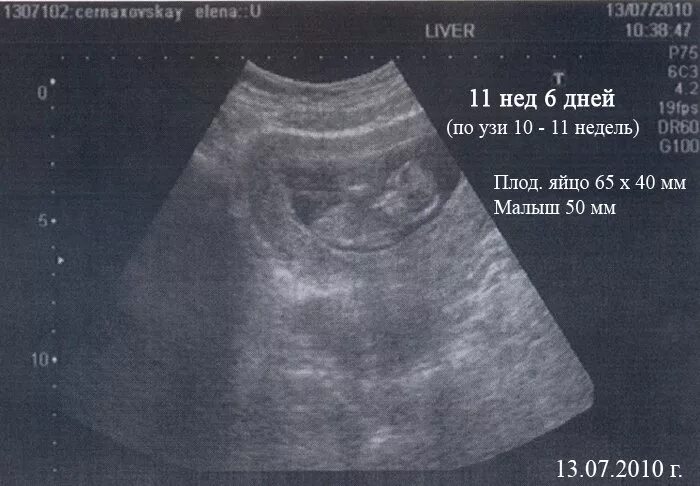

Матка 10 недель